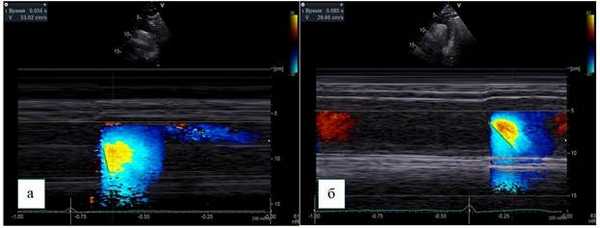

Скорость распространения потока в цветовом М-режиме определяется как отношение расстояния между точками, отображающими начало и конец наклона цветовой волны потока, ко времени между двумя этими точками (рис. 3).

Рис. 3. Супрастернальная позиция, М-ЦДК нисходящего отдела грудной аорты.

Способ определения СРП:

а - пациент без коронарного атеросклероза, СРП - 530 мм/с,

б - пациент с коронарным атеросклерозом, СРП - 296 мм/c